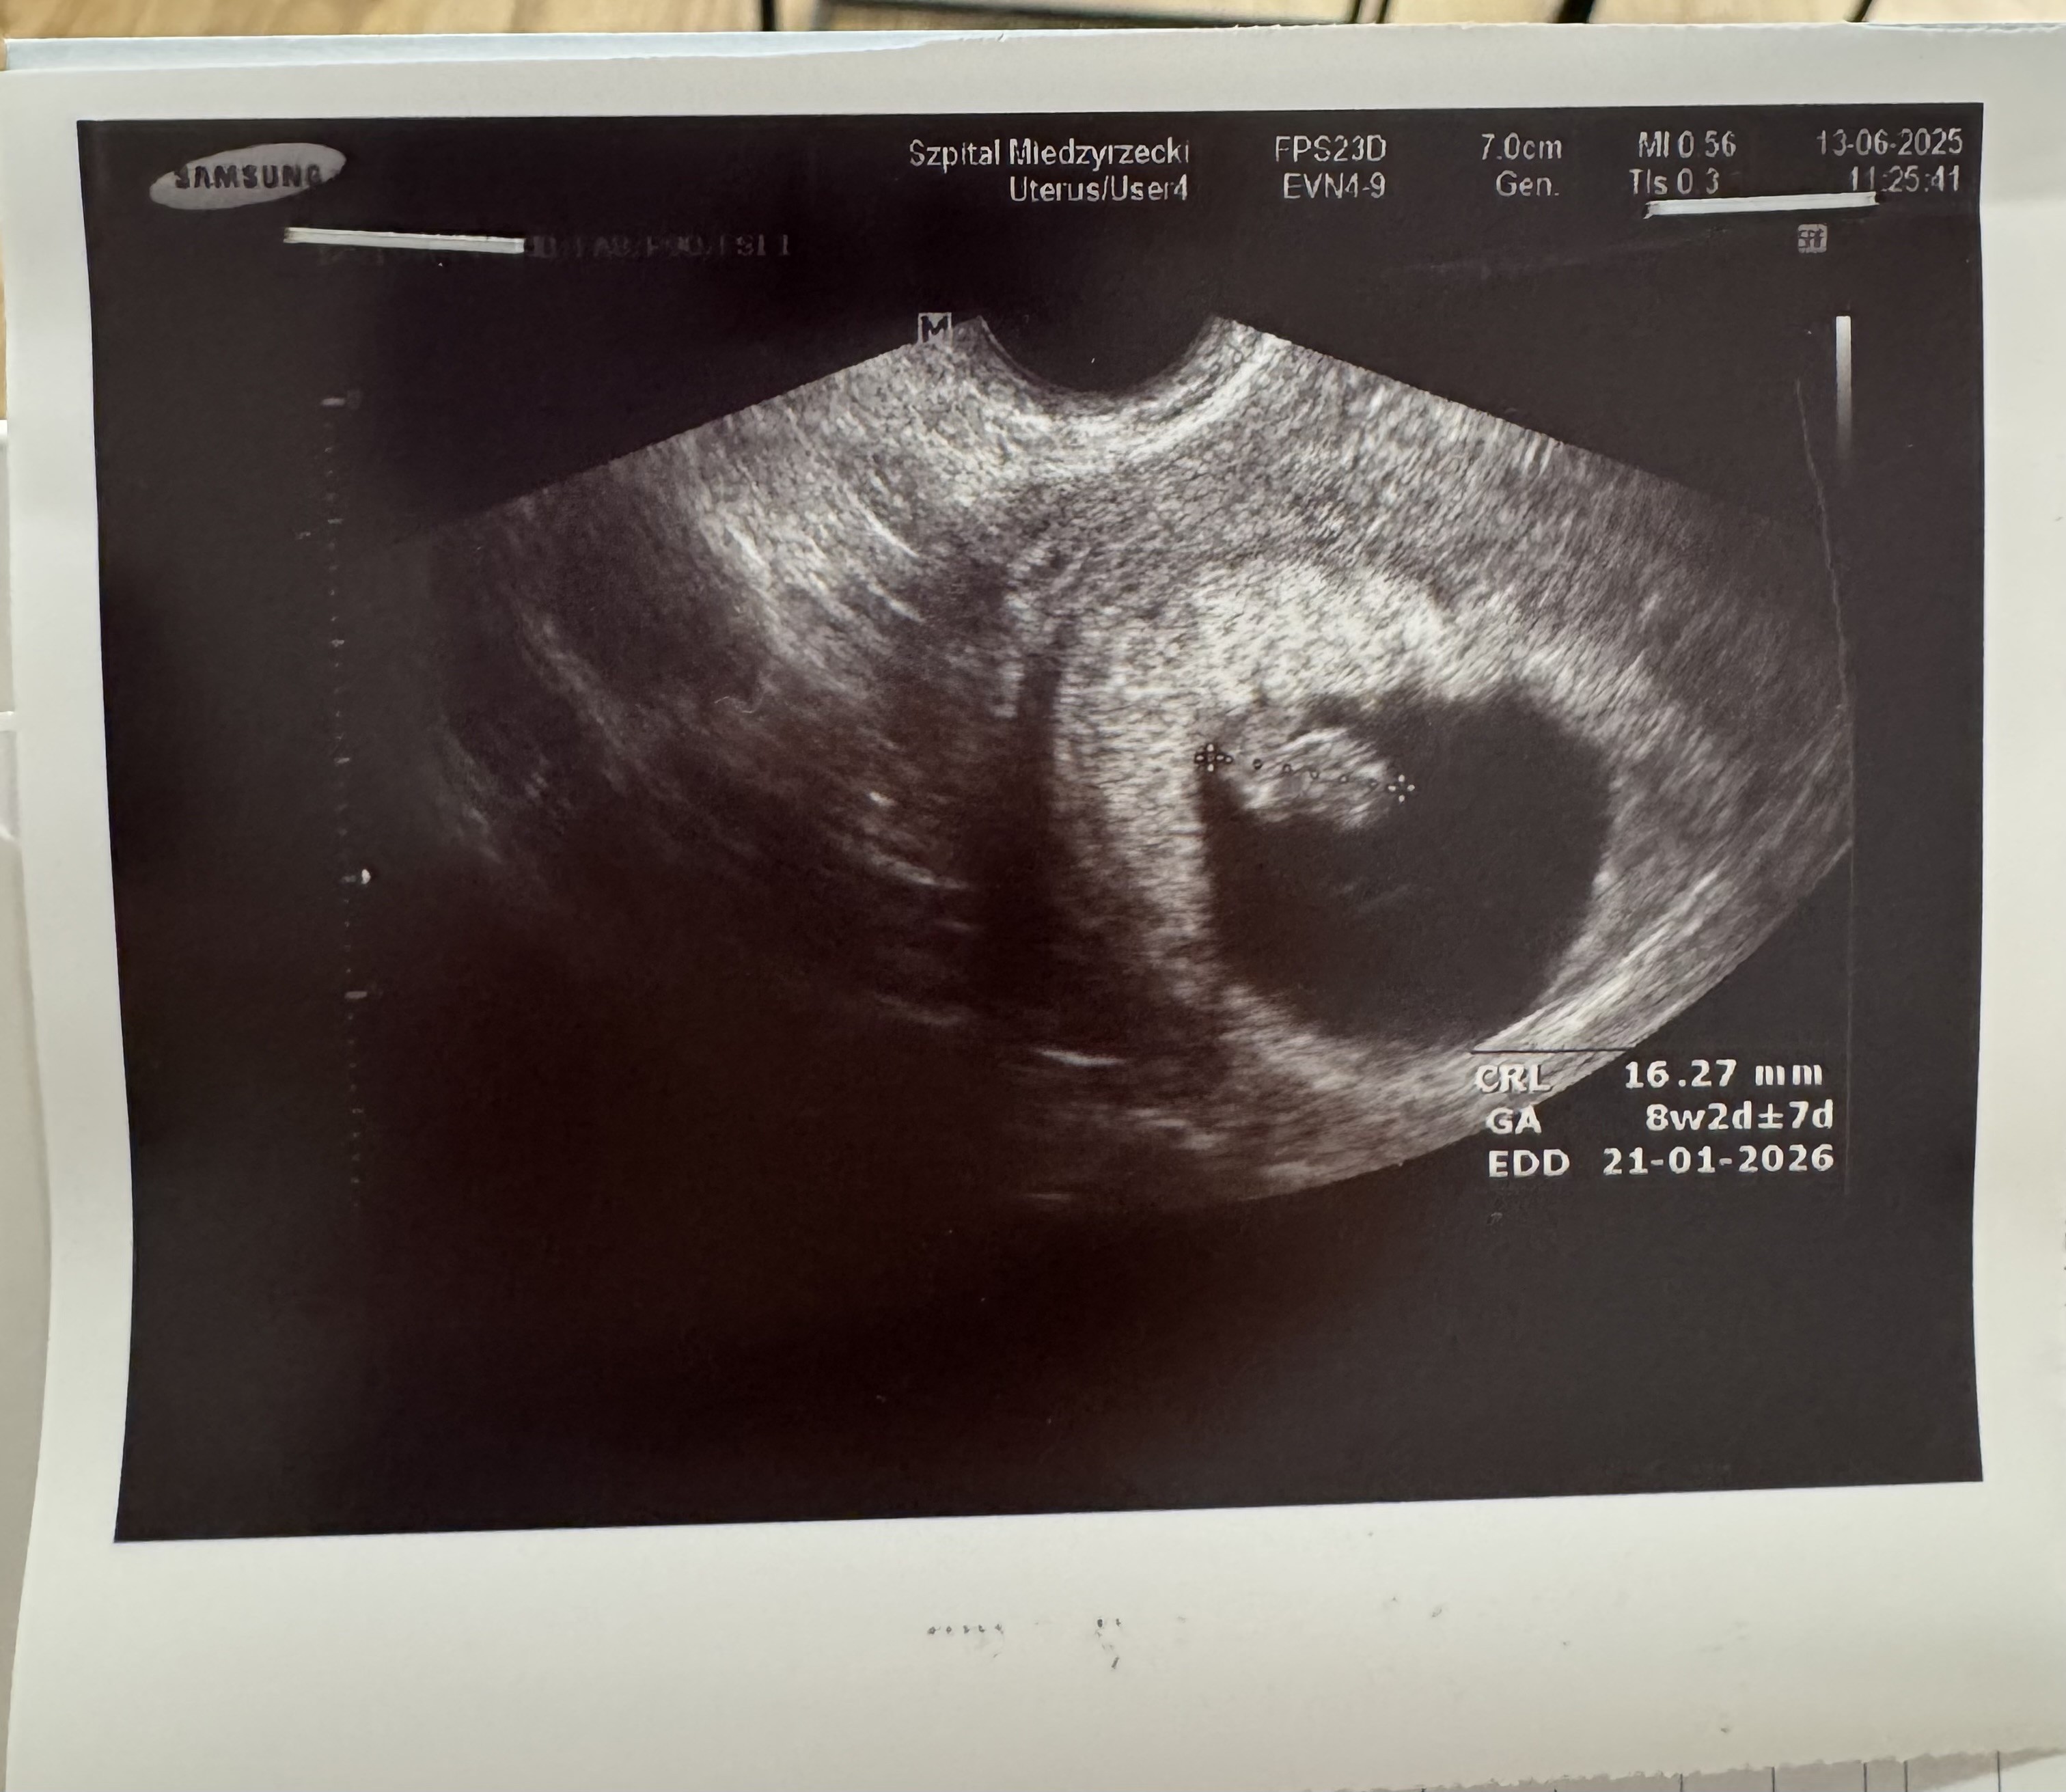

Wszystko jest ok. Dzidziuś ma 1,6cm. Serduszko ładnie biło. Założona mam kartę ciąży. Termin porodu zmienili mi z 18 na 20 stycznia więc przyjmuje już ten 20 :) choć zobaczymy co

• IMG_2003.jpeg

IMG_2003.jpeg

769,4 KB · Wyświetleń: 51